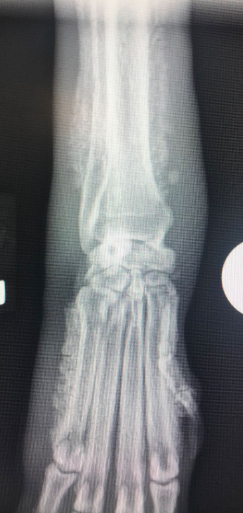

![]() | X-ray - ์ฌ์ง์์ ๊ท ์ผํ ๊ณจ๋ง ์ฆ์(uniform periosteal proliferation). - ์ฒ์์ Phalanges & metacarpal & metatarsal bones์์ ๊ด์ฐฐ๋จ. - ์งํ๋จ์ ๋ฐ๋ผ ๊ณจ๋ง ์ฆ์์ proximal(ulnar/radius, tibia/fibula)๋ก ์งํ๋จ. - Long bone์ ๊ด์ ํ๋ฉด์ ๋ณดํต ์ ์์ ์ผ๋ก ๋ณด์. |

![]() | - Firm soft tissue swelling of the distal extremities; ๋ง๋จ ์ฌ์ง์ ๋จ๋จํ ์ฐ์กฐ์ง ๋ถ์ข

ํ์ฑ. - ์์ชฝ, ๋์นญ์ ์ผ๋ก ๊ณจ๋ง ์ธ๋ถ์ ์ ์ ์กฐ์ง ํ์ฑ๋จ - ์ด๊ธฐ์๋ metatarsal/carpal bones์ ์ถ ์๋์ชฝ(abaxially)์์ ๊ด์ฐฐ. - ๋ผ์ ์ถ์ ๋ง์ฑ์ ์ธ ๊ฒฝ์ฐ ์ํฅ์ ๋ฐ์. |